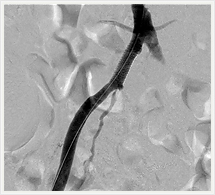

画像紹介(四肢血管治療編)

経皮的血管形成術(PTA)は先端に小さく折りたたまれたバルーンを装着したカテーテルを用いて、狭窄または閉塞してしまった血管を拡張することにより、血液の流れを確保、再開させる手技です。

この治療ではバルーンカテーテルに加えてステント(金属製のチューブ)を留置することもあります。